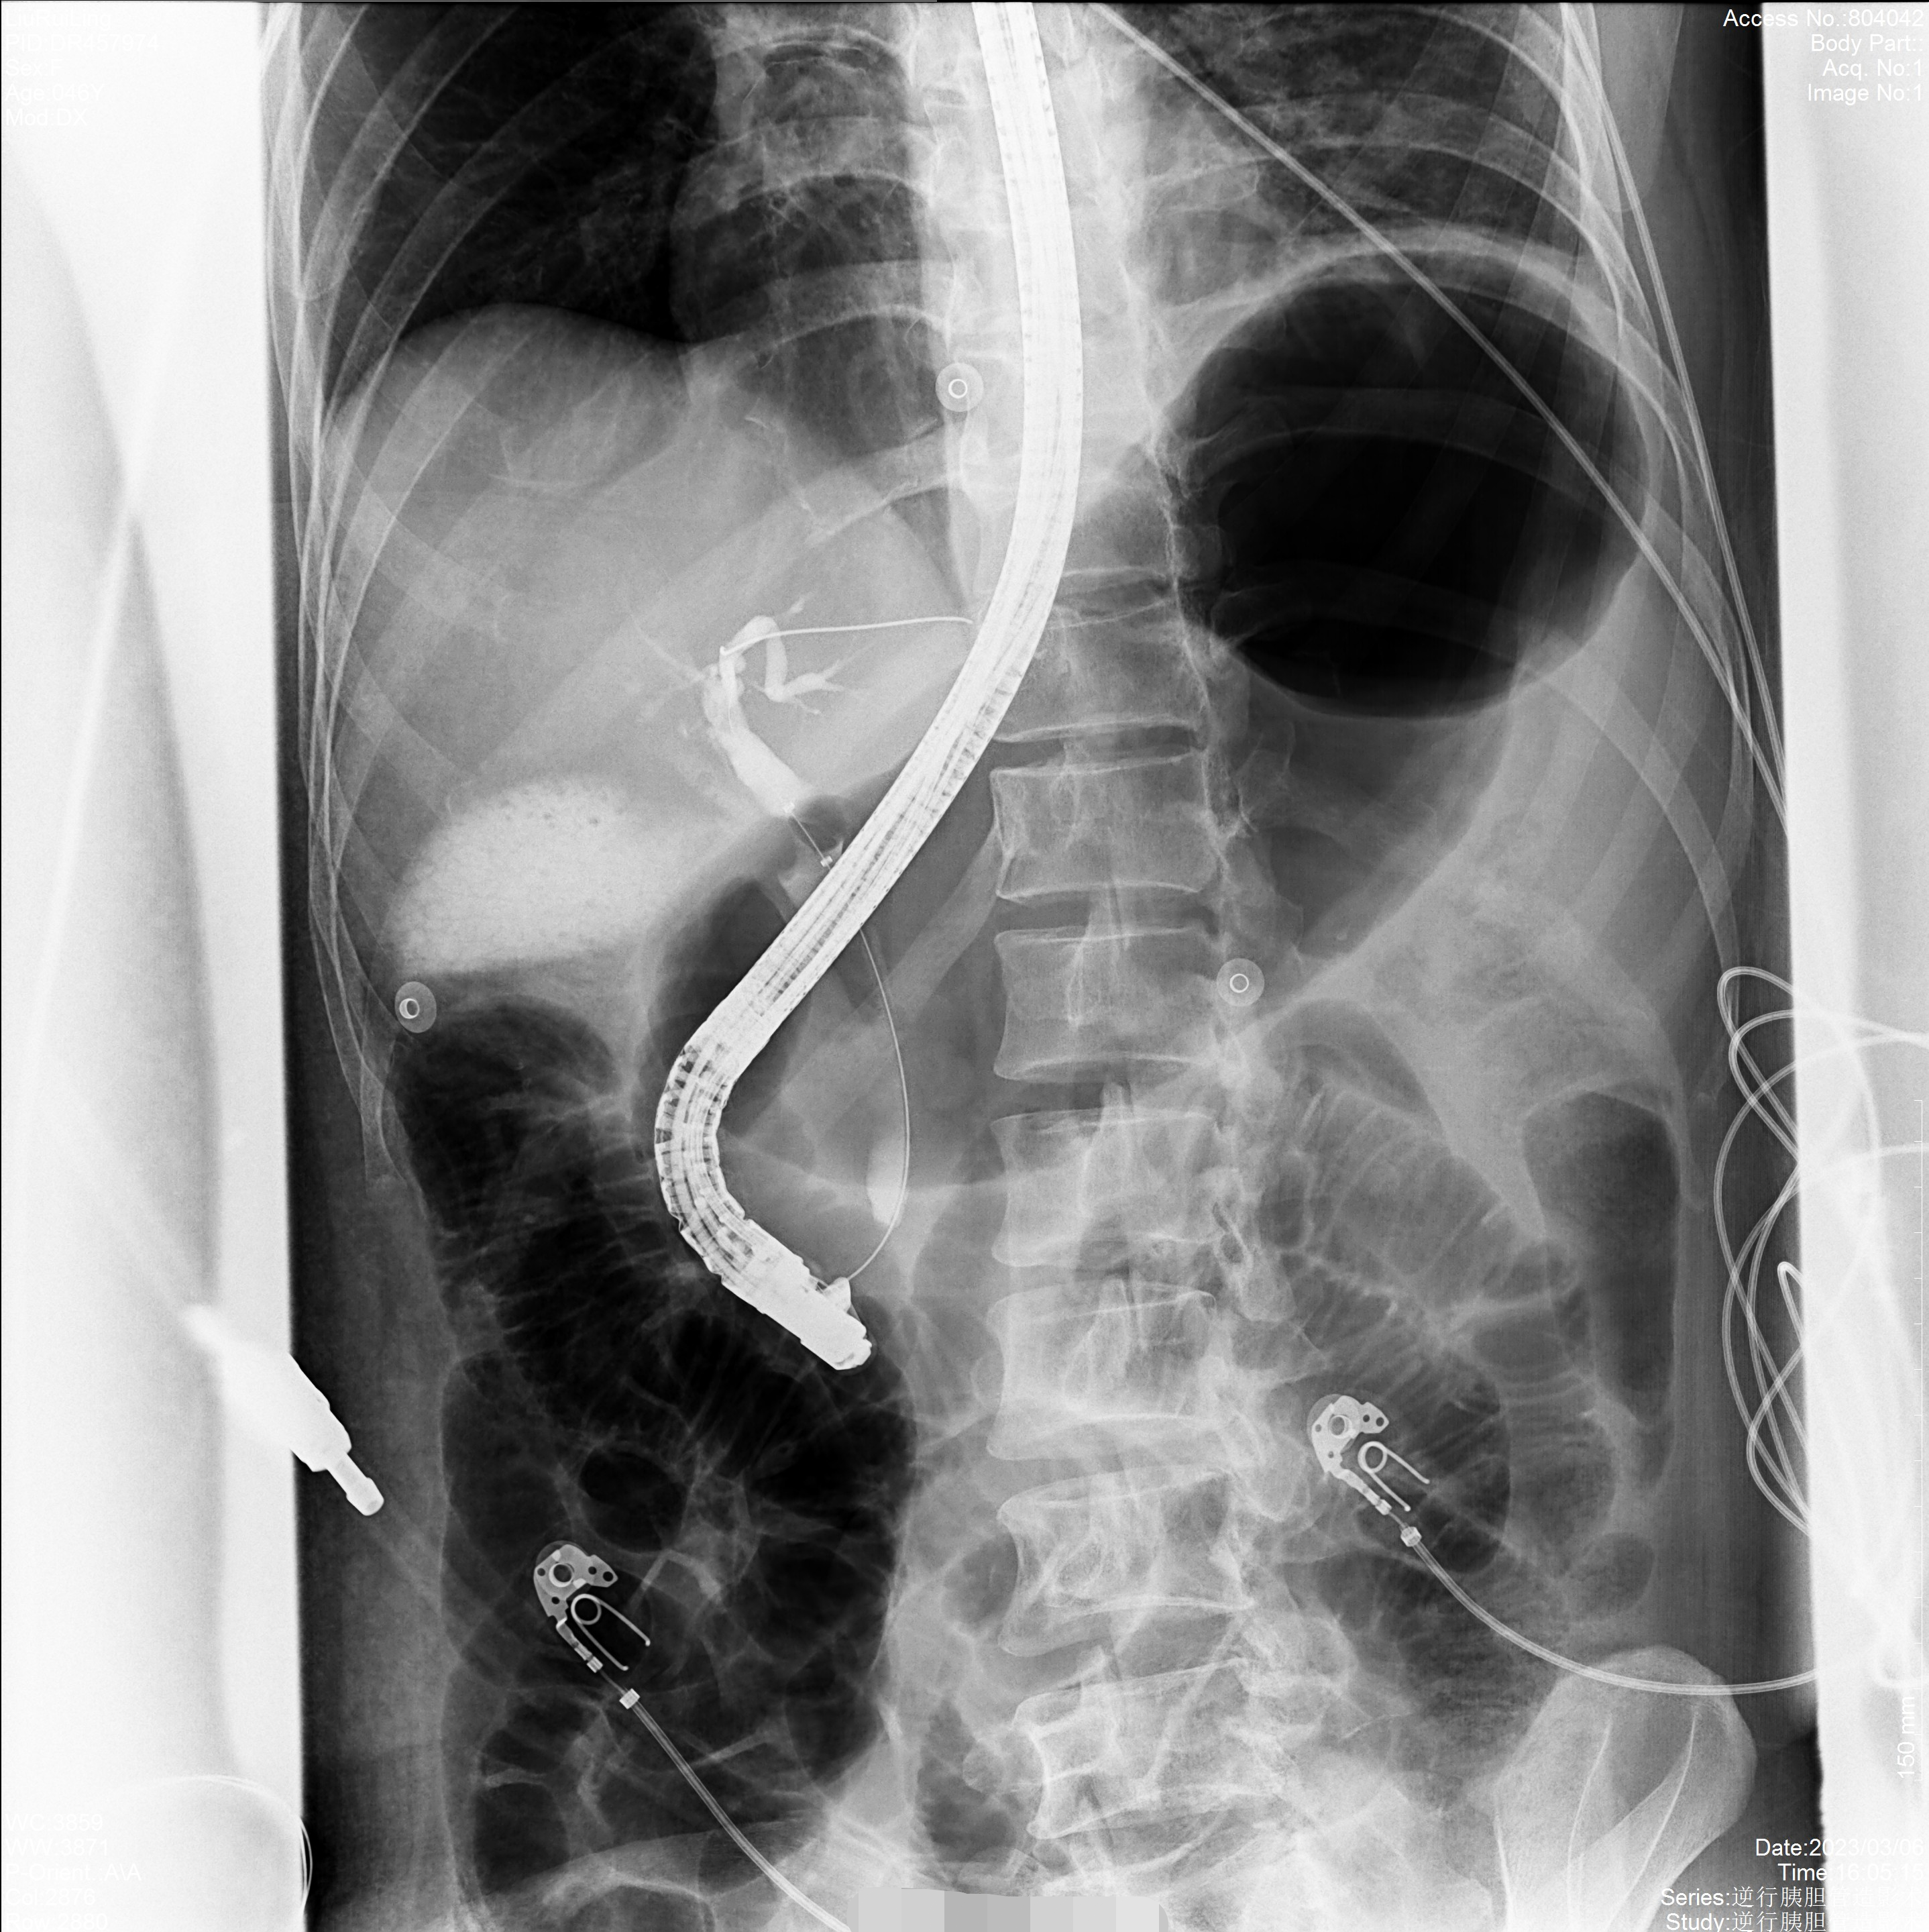

普利德多動(dòng)能動(dòng)態(tài)平板DRF具有快速成像能力,滿足圖像高質(zhì)量要求以及近臺(tái)操作安全性要求,在該設(shè)備上進(jìn)行逆行胰膽管造影術(shù)應(yīng)用,是診治胰膽疾病的可靠方法。